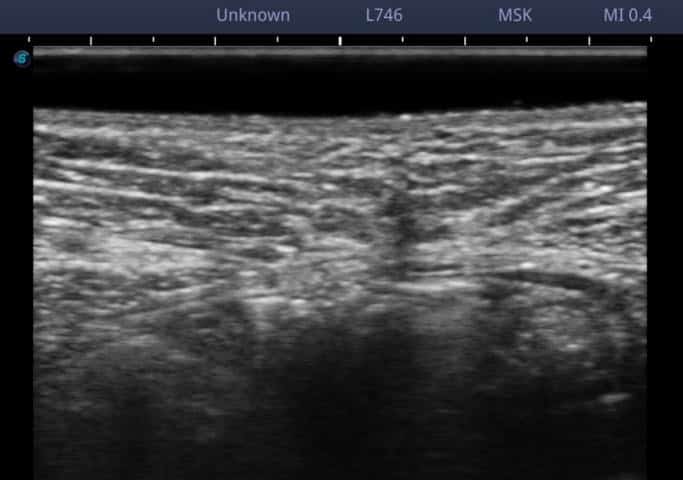

村上先生によるエコー操作の指導

正常の腹直筋

これは、正常な幅&太さの白線です。